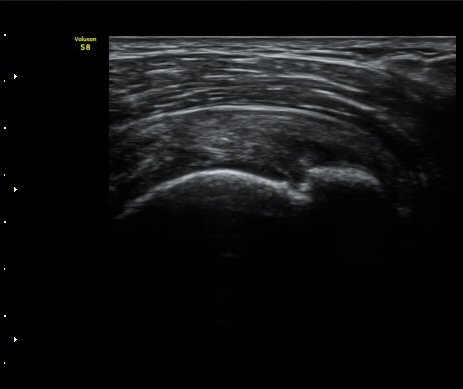

¼ºº° / ³ªÀÌ

¿©ÀÚ/ 50¼¼

ÁÖÁõ»ó

³Ñ¾îÁø ÈÄ ½ÉÇØÁö´Â ¾î±úÀÇ ÅëÁõ°ú °­Á÷

º´·Â

³Ñ¾îÁø ÈÄ ¾î±úÀÇ ÅëÁõÀÌ ¹ß»ýÇÏ¿© Ÿ º´¿ø ³»¿øÇÏ¿© ¿¢½º·¹ÀÌ °Ë»ç¿¡¼­ ƯÀÌ ¼Ò°ß ¾ø´Ù´Â ¼Ò°ßÀ» µè°í Áö³ÁÀ¸³ª ¾î±úÀÇ ÅëÁõÀÌ ½ÉÇØÁö°í Á¡Á¡ ¾î±ú°¡ ±»¾îÁ® ³»¿ø

ÃÊÀ½ÆÄ °Ë»ç